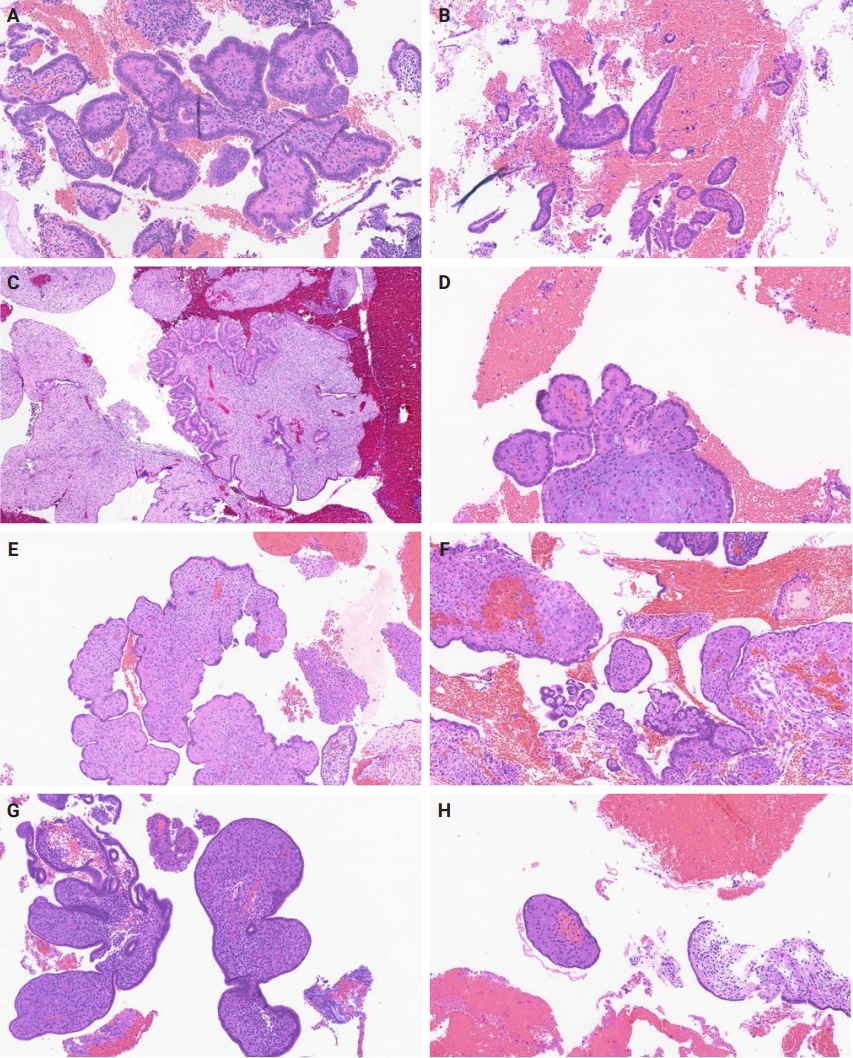

Slides for all samples (mean, 3.0 ± 2.5 slides/patient) were retrieved and reviewed jointly by the authors, inclusive of the index and all follow-up samples, with the aim of identifying the presence of papillary architecture of any type, describing their morphologic spectrum, and any concurrent pathological processes that may be present. For every case, we documented the presence of papillary structures and estimated the proportion of the specimen that they represented. A papillary structure was defined as a round, oval or filigree structure, at least 75% covered by epithelium, and harboring a stromal or fibrovascular core (Fig. 2). Large bulbous, polypoid structures with prominently pseudodecidualized stroma were not included, given that it is well recognized that such structures are common endometrial alterations associated with exogenous progestins in non-hyperplastic endometrium (Fig. 3) [17,18]. Additionally, we documented for each sample the presence of papillae branching as a surrogate indicator of architectural complexity, with subcategorization to no branching, simple (one level) branching off a central stalk irrespective of the number of such branches, and complex (≥two level) branching (i.e. the presence in the sample of at least one central stalk that gives rise to a primary branch, from which a secondary and possibly tertiary branch originate). We also evaluated other morphologic features that are relevant to the diagnoses of AH/EIN, including glandular crowding, cytologic demarcation/atypia, intraglandular architectural complexity, squamous morules, metaplastic changes, cystic structures (presence, whether they are crowded, and whether they are lined by atrophic-appearing or non-atrophic appearing epithelium), and pseudodecidual stromal change.

Fig. 2.

Morphologic spectrum of papillae with morphologic variations (A–H).

jptm-2025-09-12f2.jpg